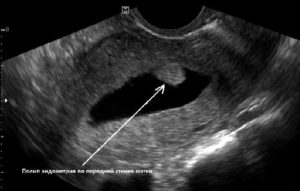

Полип эндометрия на УЗИ проявляется как достаточно четкая цилиндрическая структура белесоватого оттенка.

Как выглядит полип? К базальному слою он крепится с помощью ножки, его тело состоит из клеток эпителия. Он продолговатый, с округлой верхушкой. Когда полипов много — это называют полипозом эндометрия.Ультразвуковое обследование эффективный вид диагностики заболевания и потом делают полипэктомию.

Как говорят специалисты, полип — гиперэхогенное образование. Что это значит? Нарост имеет плотную структуру, настолько, что выделяется на фоне стенок матки светлым пятном. Ультразвук поглощается жидкостью и полостями, они на снимке темные. Чем плотнее ткани, тем более светлыми будут, например, кости ярко-белые.

Полип формируется из собственных клеток эндометрия. Причем таким образом, что содержит основу из фиброзных волокон, которые обладают высокой плотностью и заполненные промежутки железистыми клетками. Поэтому на УЗИ полип выглядит вытянутым светлым пятном цилиндрическое или пальцеобразное. Иногда можно отличить тонкую ножку образования.